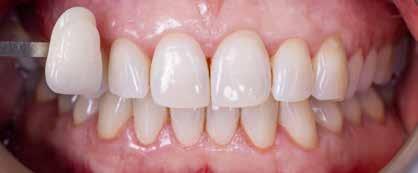

Before and after images of tooth brightening with BRILLIANT Lumina

The patient, a male in his 60s, experienced trauma against the UL1 when he was young. He had fractured part of the tooth, and had needed a crown.

He was asymptomatic for many years following his injury. Although he had received a lot of restorative treatment, the patient’s overall oral health was fair. The main concern was the UL1, which had become discoloured over time, turning yellow and brown.